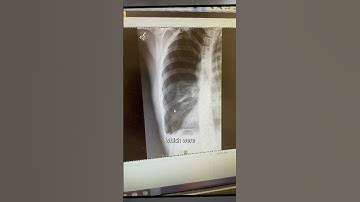

Vaping teenager COLLAPSES and bursts hole in lung